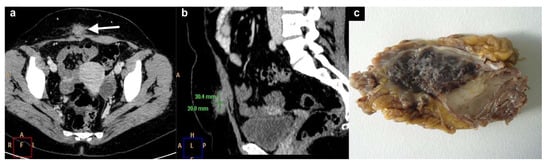

4. Subcutaneous Endometriosis

5. Intramuscular Endometriosis